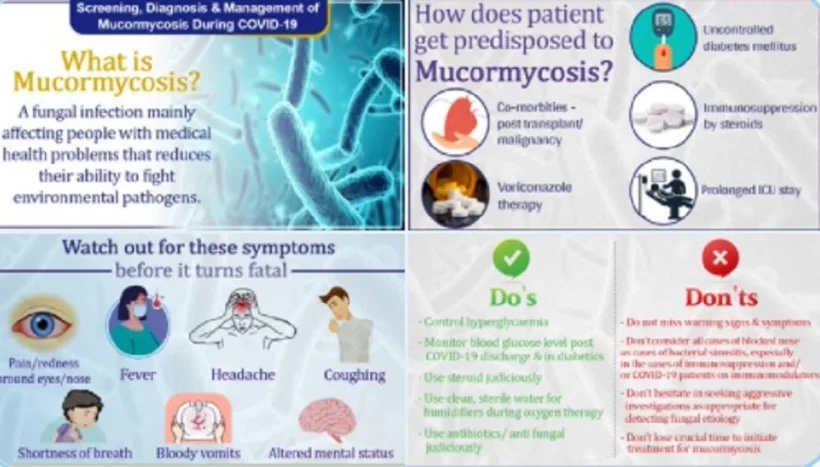

क्या है म्यूकरमाइकोसिस– म्यूकरमाइकोसिस एक ऐसा फंगल इंफेक्शन है जिसे कोरोना वायरस ट्रिगर करता है. कोविड-19 टास्क फोर्स के एक्सपर्ट्स का कहना है कि ये उन लोगों में आसानी से फैल जाता है जो पहले से किसी ना किसी बीमारी से जूझ रहे हैं और जिनका इम्यून सिस्टम कमजोर होता है. इन लोगों में इंफेक्शन से लड़ने की क्षमता कम होती है.

किन लोगों को खतरा– इंडियन काउंसिल ऑफ मेडिकल रिसर्च के मुताबिक, कुछ खास कंडीशन में ही कोरोना मरीजों में म्यूकरमाइकोसिस का खतरा बढ़ता है. अनियंत्रित डायबिटीज, स्टेरॉयड की वजह से कमजोर इम्यूनिटी, लंबे समय तक आईसीयू या अस्पताल में दाखिल रहना, किसी अन्य बीमारी का होना, पोस्ट ऑर्गेन ट्रांसप्लांट, कैंसर या वोरिकोनाजोल थैरेपी (गंभीर फंगल इंफेक्शन का इलाज) के मामले में ब्लैक फंगस का खतरा बढ़ सकता है.

क्या हैं लक्षण– ब्लैक फंगस में मुख्य रूप से कई तरह के लक्षण देखे जाते हैं. आंखों में लालपन या दर्द, बुखार, सिरदर्द, खांसी, सांस में तकलीफ, उल्टी में खून या मानसिक स्थिति में बदलाव से इसकी पहचान की जा सकती है. इसलिए इन लक्षणों पर बारीकी से गौर करना चाहिए.

ब्लैक फंगस से बचने के लिए क्या करें– हाइपरग्लीसीमिया (ब्लड शुगर) को कंट्रोल रखें. कोविड-19 से रिकवरी के बाद भी ब्लड ग्लूकोज का लेवल मॉनिटर करते रहें. स्टेरॉयड का इस्तेमाल सिर्फ डॉक्टर्स की सलाह पर ही करें. ऑक्सीजन थैरेपी के दौरान ह्यूमिडिटीफायर के लिए साफ पानी का ही इस्तेमाल करें. एंटीबायोटिक्स या एंटीफंगल दवाओं का इस्तेमाल जरूरत पड़ने पर ही करें.

क्या न करें– ब्लैक फंगस से बचने के लिए इसके लक्षणों को बिल्कुल नजरअंदाज न करें. बंद नाक वाले सभी मामलों को बैक्टीरियल साइनसाइटिस समझने की भूल न करें. खासतौर से कोविड-19 और इम्यूनोसप्रेशन के मामले में ऐसी गलती न करें.

फंगल एटियोलॉजी का पता लगाने के लिए KOH टेस्ट और माइक्रोस्कोपी की मदद लेने से न घबराएं. यदि डॉक्टर्स इसका तुरंत इलाज करने की सलाह दे रहे हैं तो उसे इग्नोर न करें. रिकवरी के बाद भी इसके बताए गए लक्षणों को अनदेखा न करें, क्योंकि कई मामलों में फंगल इंफेक्शन रिकवरी के एक सप्ताह या महीनेभर बाद भी उभरते देखा गया है.